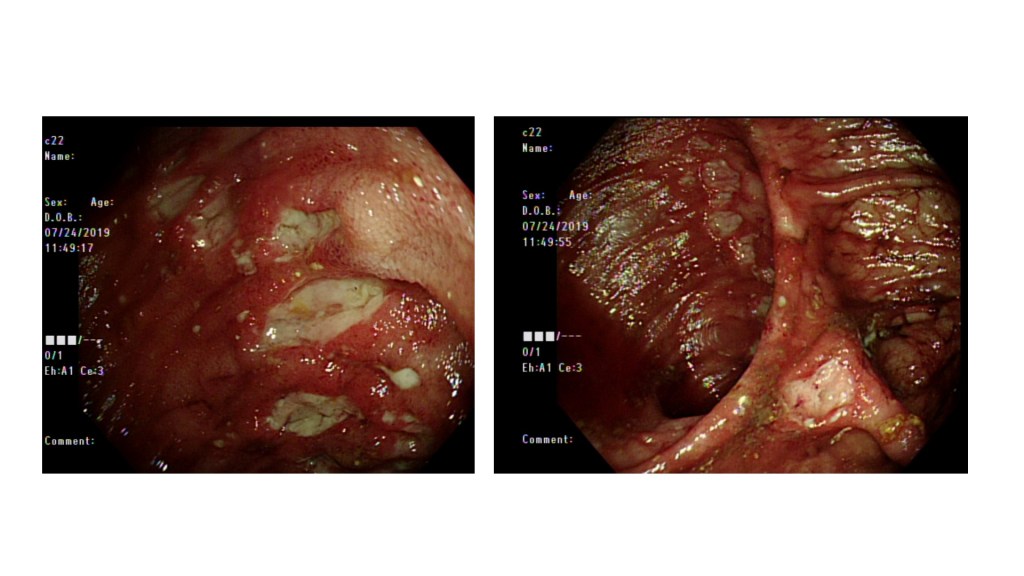

我這次報告的病患是Behçet’s disease with multiple organ involvement, 這是一個40歲女性,11年前診斷Behçet’s disease,症狀表現包含口腔潰瘍、生殖器潰瘍,眼部病變、腸胃道潰瘍、出血以及穿孔,腎臟及脾臟多個血管瘤合併血管瘤破裂出血,栓塞過2兩次、脾臟炎以及小腿脛前壞疽性膿皮症等等,幾乎可以在教科書上看到的病變都可以在這個病人身上看到,在八月時我剛好在風濕免疫科病房照顧這位病人,她在住院後又出現脾臟血管瘤破裂以及大腸出血等併發症,最後infliximab IVF後轉至腸胃科病房照顧。